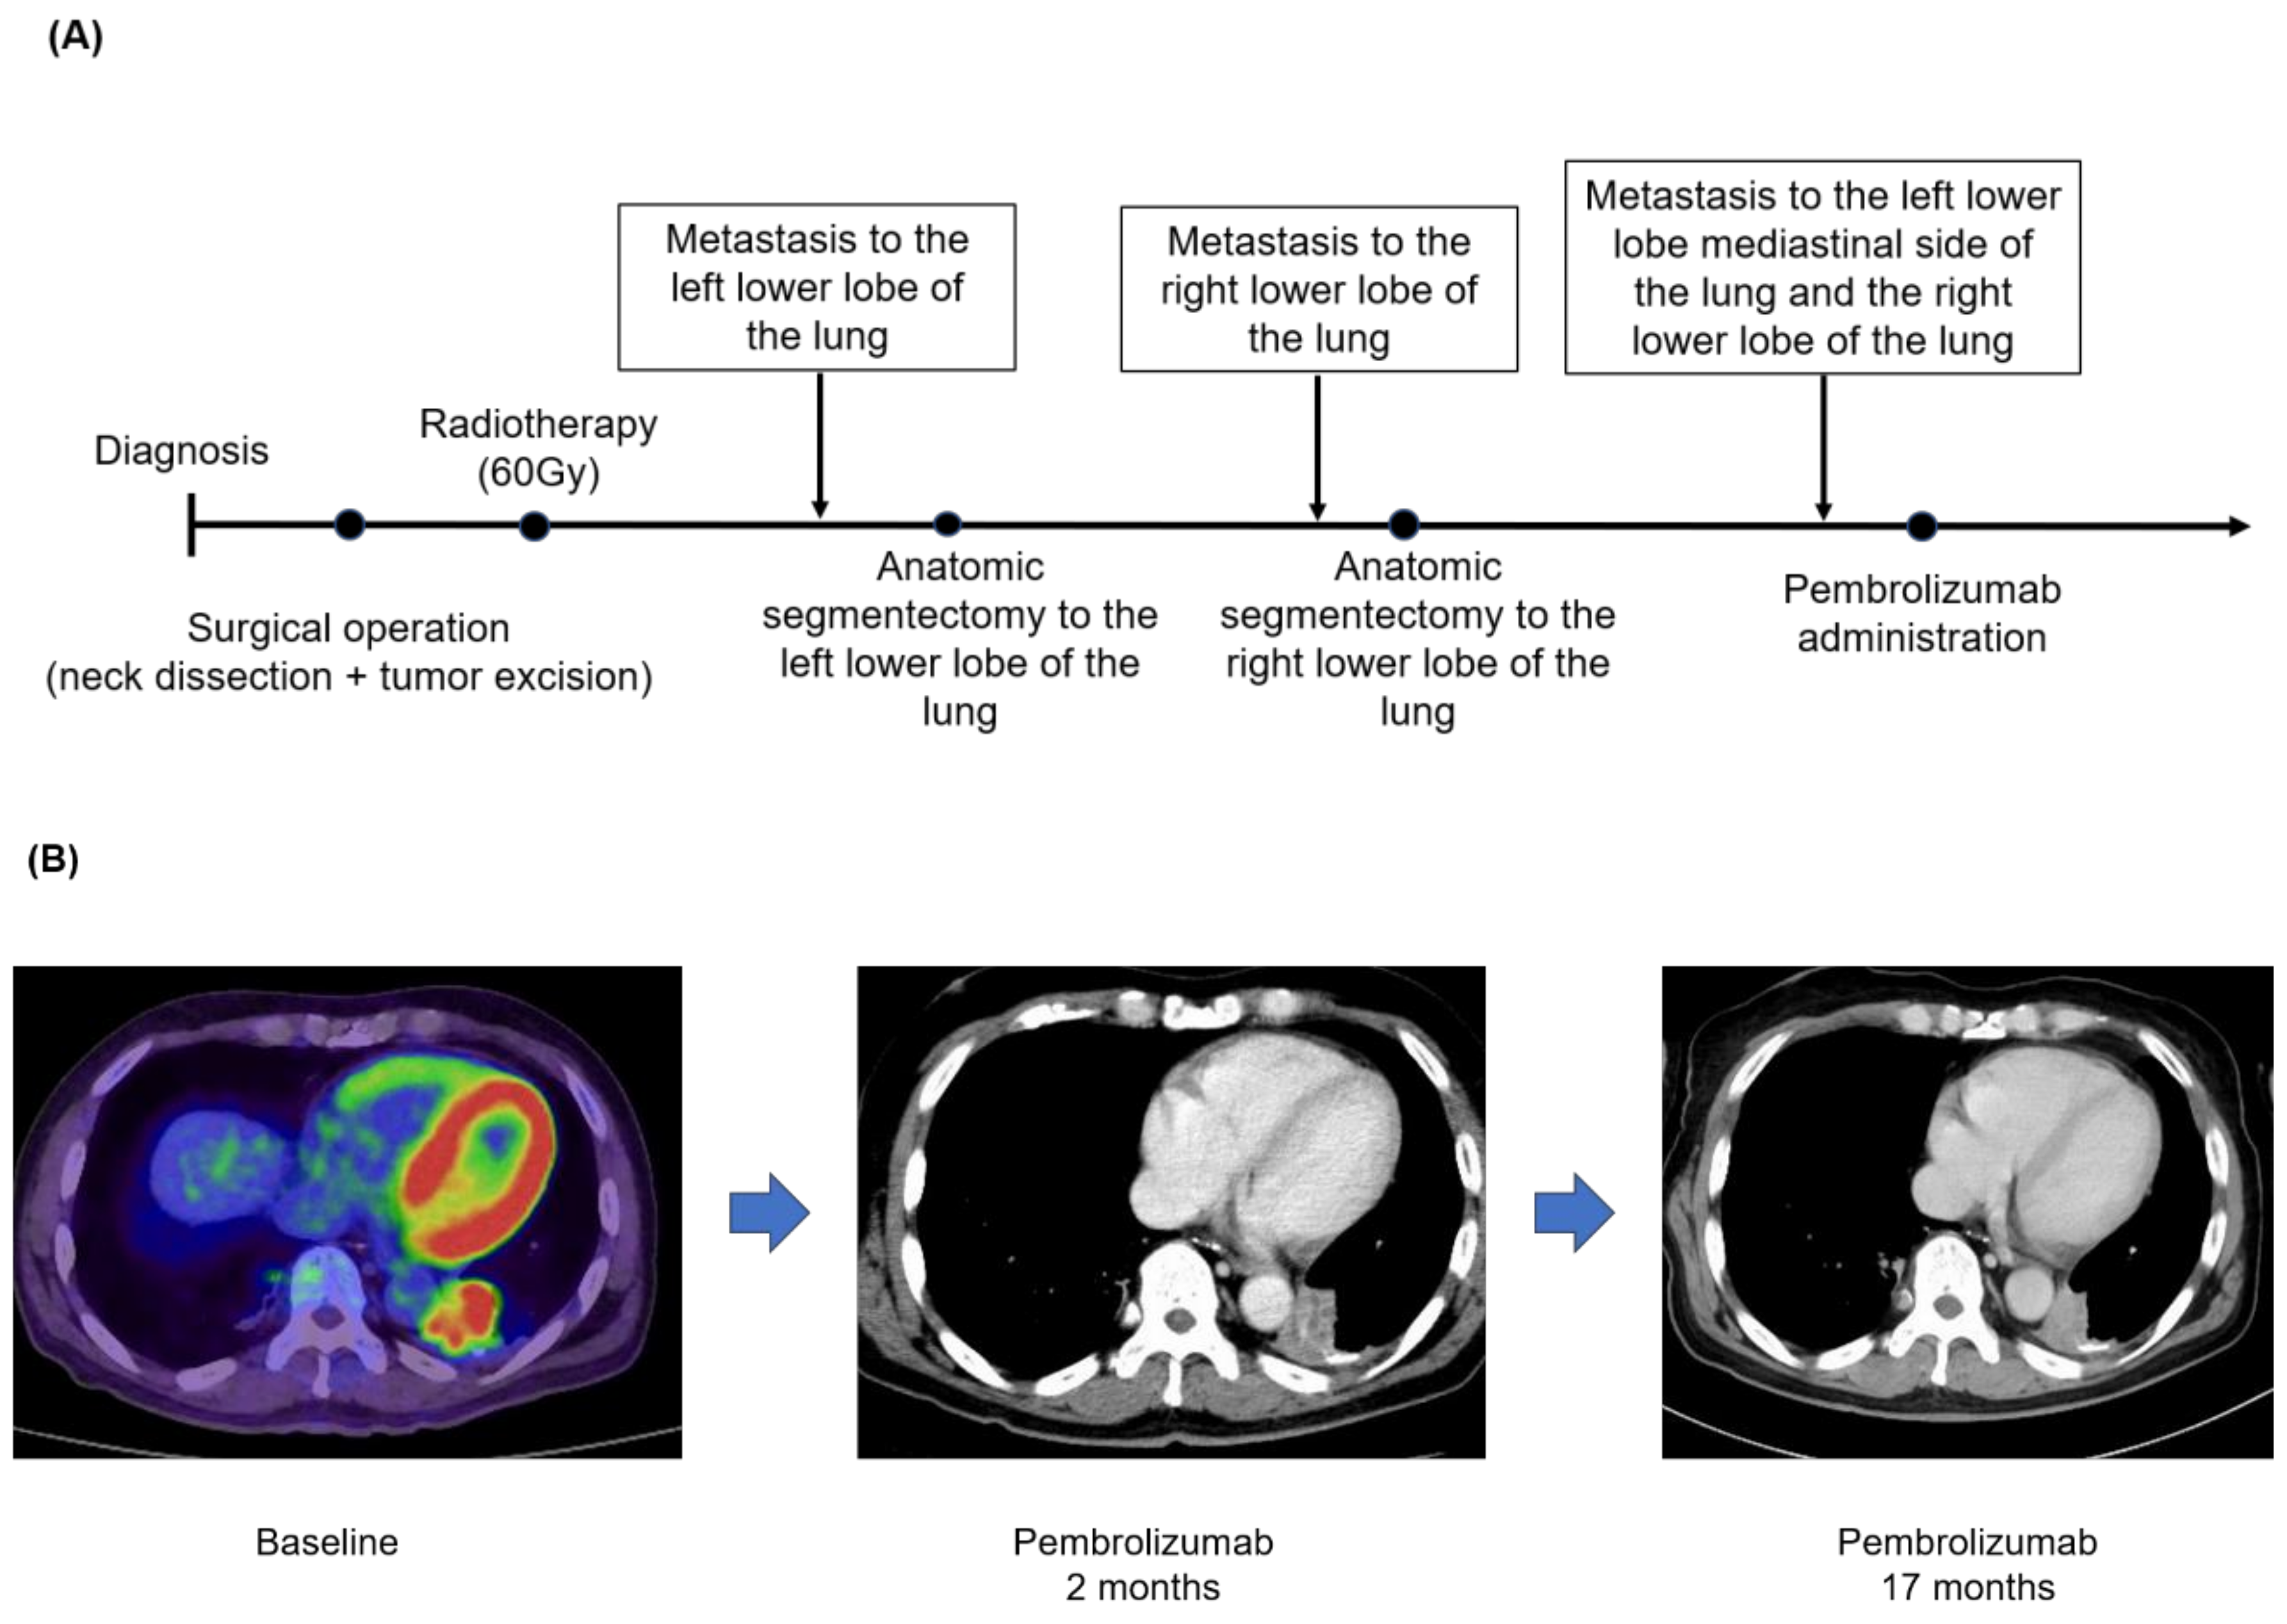

3.4. Case Presentation (Case No.3 in Table 5A,B)

| 3 | 63/M | 2 mut/Mb | Pembrolizumab | 1st line | PR |

| 3 | BRAF G469A EP300 R202* MLL2 G61fs*69 MYB-NFIB fusion MYB rearrangement intron 14 NOTCH1 H2428fs*6 TERT promoter -124C>T TP53 C176W-subclonal | |||||